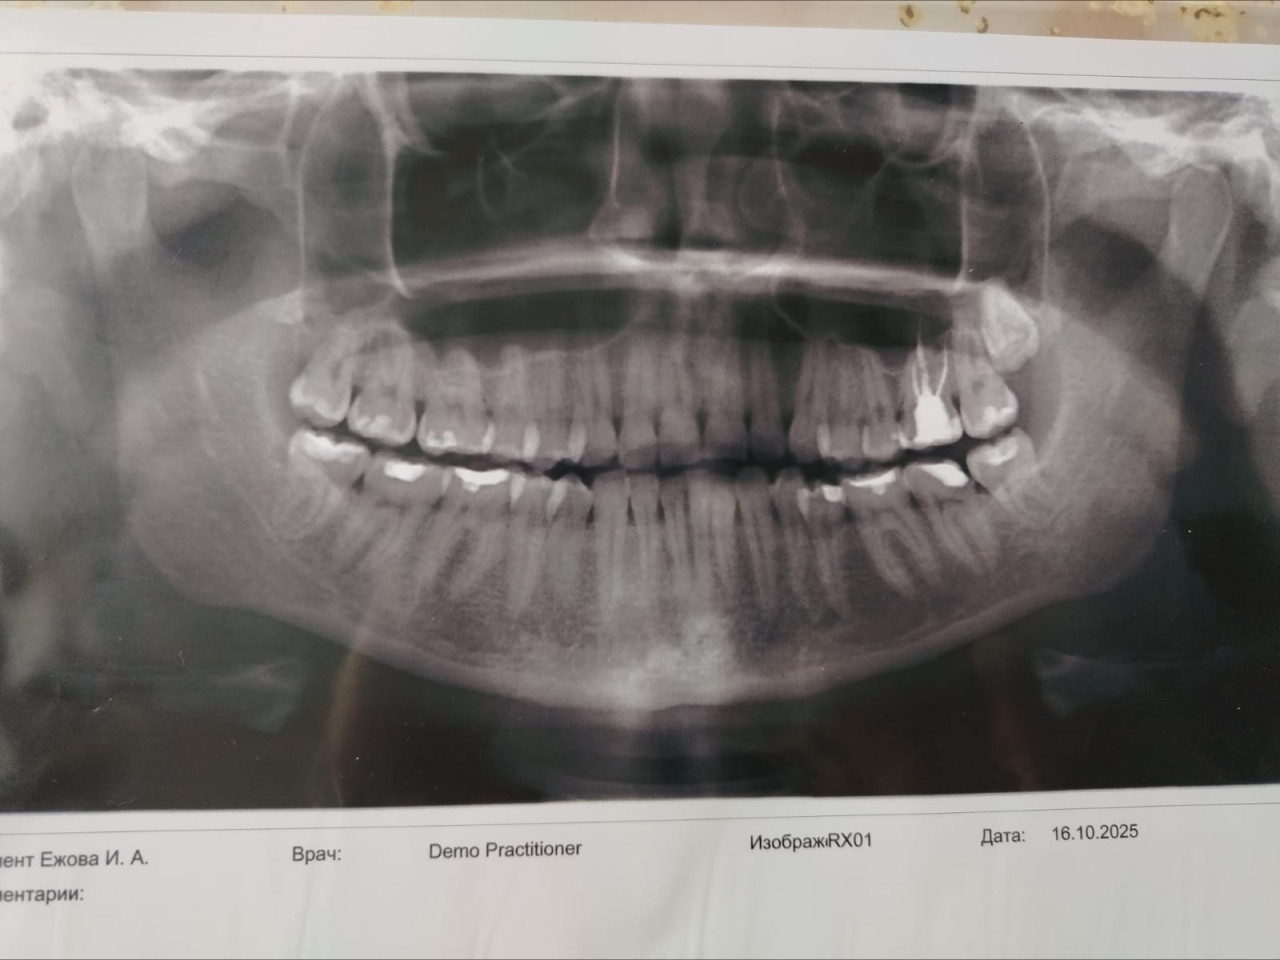

Добрый день! Собираюсь устанавливать брекеты, но проблема в том, что не прорезался 1 зуб мудрости. Растёт он ровно, как, в принципе, и выросли 3 остальных зуба. Ортодонт говорит, чтобы я удаляла непрорезавшийся зуб. Посоветовалась со стоматологом-хирургом-челюстно - лицевым хирургом, на что он мне сказал, что зуб не мешает и так как зуб ещё внутри, то мы просто "раскурочим" челюсть.

Есть ли возможность поставить все - таки брекеты в таком случае? И какой риск, что после снятия брекетов и прорезывания последней восьмёрки зубы подвинутся? Фото снимка прикладываю.

Здравствуйте. По снимку видно, что зуб мудрости действительно расположен ровно и не оказывает давления на соседние зубы. В таких случаях установка брекетов возможна без удаления, если ортодонт учтёт это при планировании лечения. Риск смещения зубов после прорезывания минимален, но для контроля желательно периодически делать снимки и наблюдаться у врача и если восьмёрка начнёт менять положение, её можно удалить позже без вреда для прикуса.

Здравствуйте. По вашему снимку непрорезавшийся зуб мудрости расположен правильно и не оказывает патологического давления. Устанавливать брекеты можно и без его удаления, если ортодонт скорректирует план лечения с учётом его положения. Однако стоит понимать, что при дальнейшем прорезывании зуб может вызвать лёгкое смещение ряда, поэтому важно наблюдаться у ортодонта и периодически делать контрольные снимки.